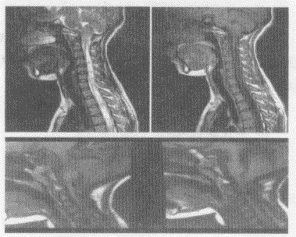

5.患者,男,30歲,兩手乏力、發(fā)麻,結(jié)合圖像,最可能的診斷是

正確答案:A